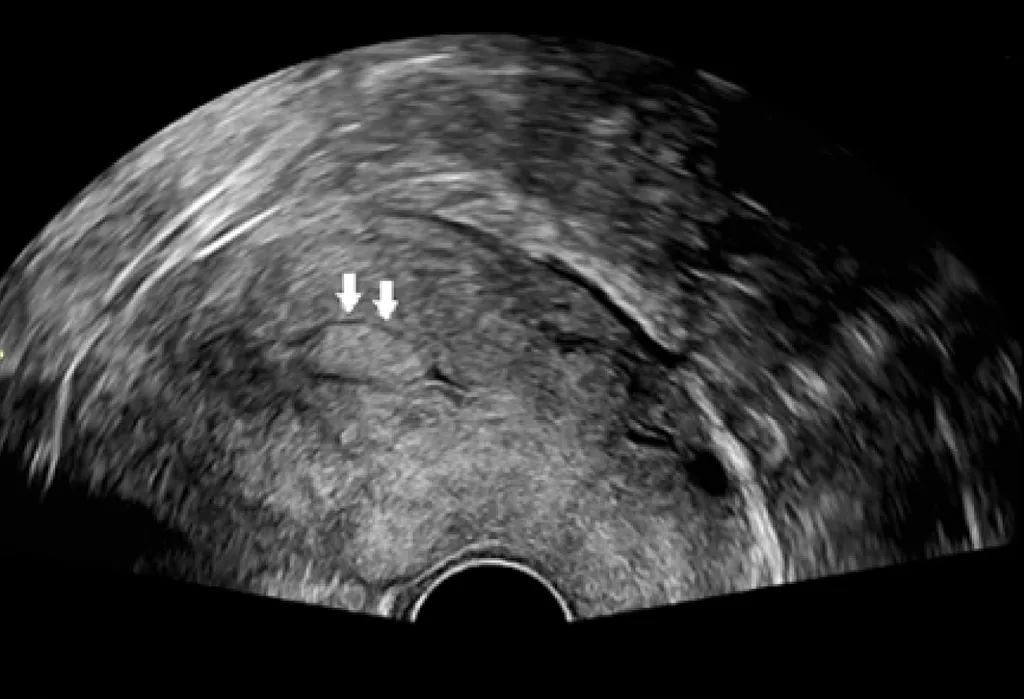

【115-1 醫學(六) 第47題】一個 33 歲女性來到門診,她主訴為長期有經期時間過長及間斷性子宮出血之症狀,此外她並無經血量過多或頻尿之現象,3 個月前子宮抹片檢查為正常。她的經期剛結束,經婦科超音波檢查發現如圖,下列何者是最有可能的診斷?